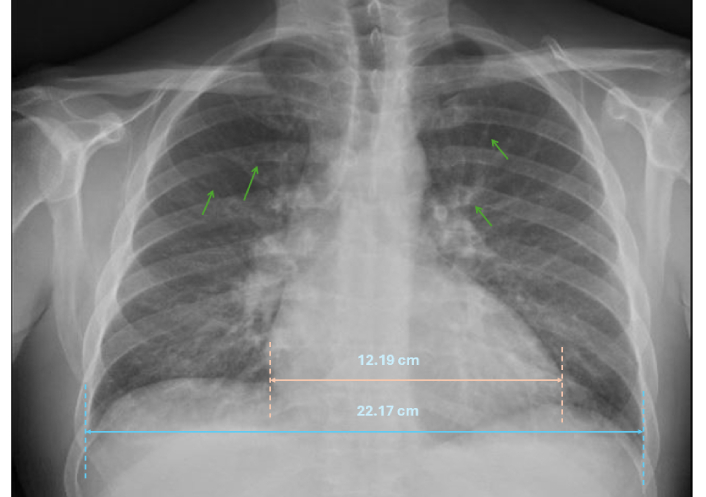

Baseline laboratory investigations demonstrated mildly elevated inflammatory markers, which were non-specific in nature (Table 1). Initial chest radiography performed during early emergency department presentations was unremarkable. However, repeat imaging later during the admission demonstrated evolving pulmonary changes consistent with acute heart failure (Figure 2).

Chest X-ray demonstrating cardiomegaly with upper lobe diversion (thin green arrows).